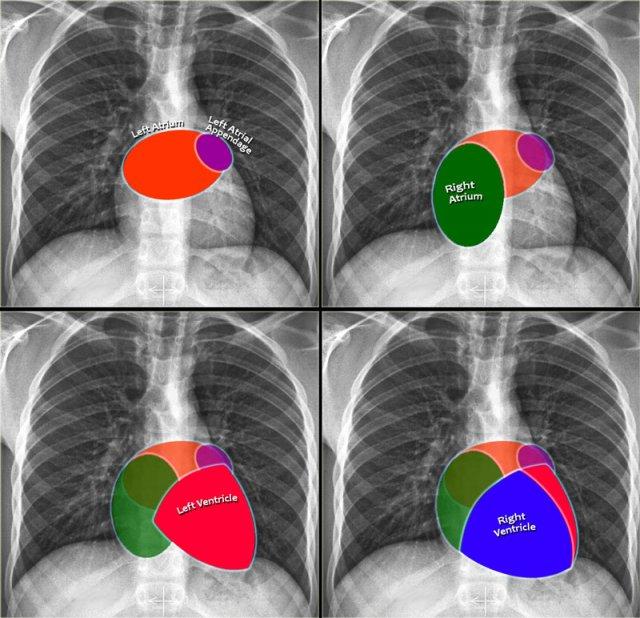

Tim và Màng Ngoài Tim

Bờ Tim trên X-quang Ngực Thẳng

Trên phim X-quang ngực thẳng tiêu chuẩn, chỉ có thể quan sát được bờ ngoài của tim. Trong hầu hết các trường hợp, chúng ta có thể đánh giá kích thước tổng thể của tim và bóng tim, nhưng việc đánh giá từng buồng tim riêng lẻ là khó khăn. Tuy nhiên, hiểu biết về vị trí giải phẫu của các buồng tim giúp ích cho việc phân tích các thay đổi về hình dạng và bờ tim liên quan đến giãn buồng tim.

Nhĩ Trái (NT)

Đây là buồng tim nằm sau nhất, nhận máu đã được oxy hóa từ các tĩnh mạch phổi đổ vào nhĩ trái theo hướng gần như nằm ngang. Tiểu nhĩ trái đôi khi có thể nhìn thấy như một phần lồi nhỏ ngay bên dưới thân động mạch phổi (thấy rõ nhất trên tư thế nghiêng).

Dấu hiệu X-quang của giãn nhĩ trái:

- Tư thế thẳng (PA): Phồng bờ tim phải phía trên và mở rộng góc carina do hai phế quản gốc bị đẩy ra hai bên.

- Tư thế nghiêng: Phồng bờ tim sau-trên.

Nhĩ Phải (NP)

Nhận máu thiếu oxy từ tĩnh mạch chủ trên và tĩnh mạch chủ dưới.

Dấu hiệu X-quang của giãn nhĩ phải:

- Tư thế thẳng (PA): Bờ tim phải bị đẩy ra ngoài.

Thất Trái (TT)

Nằm ở phía sau và bên trái so với thất phải.

Dấu hiệu X-quang của giãn thất trái:

- Tư thế thẳng (PA): Bóng tim mở rộng sang trái

- Tư thế nghiêng: Phồng bờ tim dưới-sau.

Thất Phải (TP)

Vị trí: Buồng tim nằm trước nhất, ngay sau xương ức.

Dấu hiệu X-quang của giãn thất phải:

- Tư thế thẳng (PA): Giãn có thể đẩy bóng tim sang trái, trong các trường hợp nặng, bờ tim trái có thể được tạo thành bởi thất phải.

- Tư thế nghiêng: Lấp đầy khoang sau xương ức tiến triển dần, bắt đầu từ phía dưới và lan lên trên khi thất phải giãn to hơn.

Bờ Từng Buồng Tim trên Tư Thế Nghiêng

- Nhĩ Trái: Tạo thành bờ tim sau-trên; giãn gây phồng ra phía sau.

- Thất Trái: Tạo thành bờ tim sau-dưới; giãn gây di lệch ra sau-dưới.

- Thất Phải: Chiếm khoang sau xương ức phía dưới; giãn lấp đầy khoang sáng sau xương ức theo hướng từ dưới lên trên.